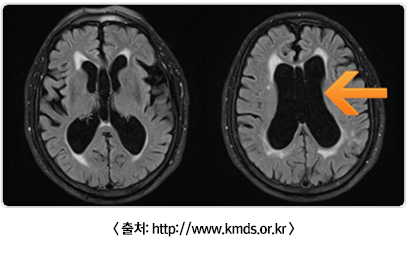

MRI 검사

• - 파킨슨병의 경우에는 MRI가 정상소견인 반면에 다른 질환들은 특징적인 MRI 소견을 보입니다.

• 1) 정상압 뇌 수두증 : 뇌안에 정상적으로 존재하는 빈 공간이 있는데 이 부위를 뇌실이라고 한다. 정상압수두증이 있으면, 이러한 뇌실 부위가 비정상적으로 증가하여 (화살표) 뇌를 압박하면서 보행장애, 요실금, 기억력 장애 등을 보일 수 있습니다.